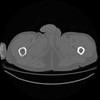

5 CUERPO,CE,Vol,1.0,CUERPO,,